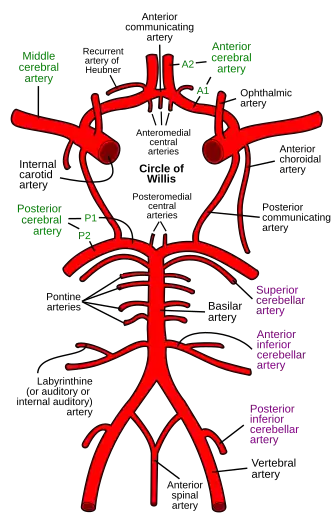

| Source | Vertebral arteries |

In human anatomy, the anterior spinal artery is the artery that supplies the anterior portion of the spinal cord. It arises from branches of the vertebral arteries and courses along the anterior aspect of the spinal cord. It is reinforced by several contributory arteries, especially the artery of Adamkiewicz.

The anterior spinal artery arises bilaterally as two small branches near the termination of the vertebral arteries. One of these vessels is usually larger than the other, but occasionally they are about equal in size.

Descending in front of the medulla oblongata, they unite at the level of the foramen magnum. The single trunk descends in the front of the medulla spinalis, extending to the lowest part of the medulla spinalis. It is continued as a slender twig on the filum terminale. The vessel passes in the pia mater along the anterior median fissure.

Branches

On its course the artery takes several small branches (i.e. anterior segmental medullary arteries), which enter the vertebral canal through the intervertebral foramina. These branches are derived from the vertebral artery, the ascending cervical artery, a branch of the inferior thyroid artery in the neck, the intercostal arteries in the thorax, and from the lumbar artery, iliolumbar artery and lateral sacral arteries in the abdomen and pelvis.